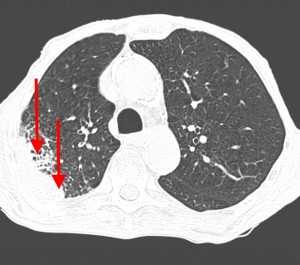

Пример контактного распространения опухоли: мезотелиома плевры, прорастающая в верхнюю легочную долю и грудную стенку. Спиральная компьютерная томография (МСКТ).